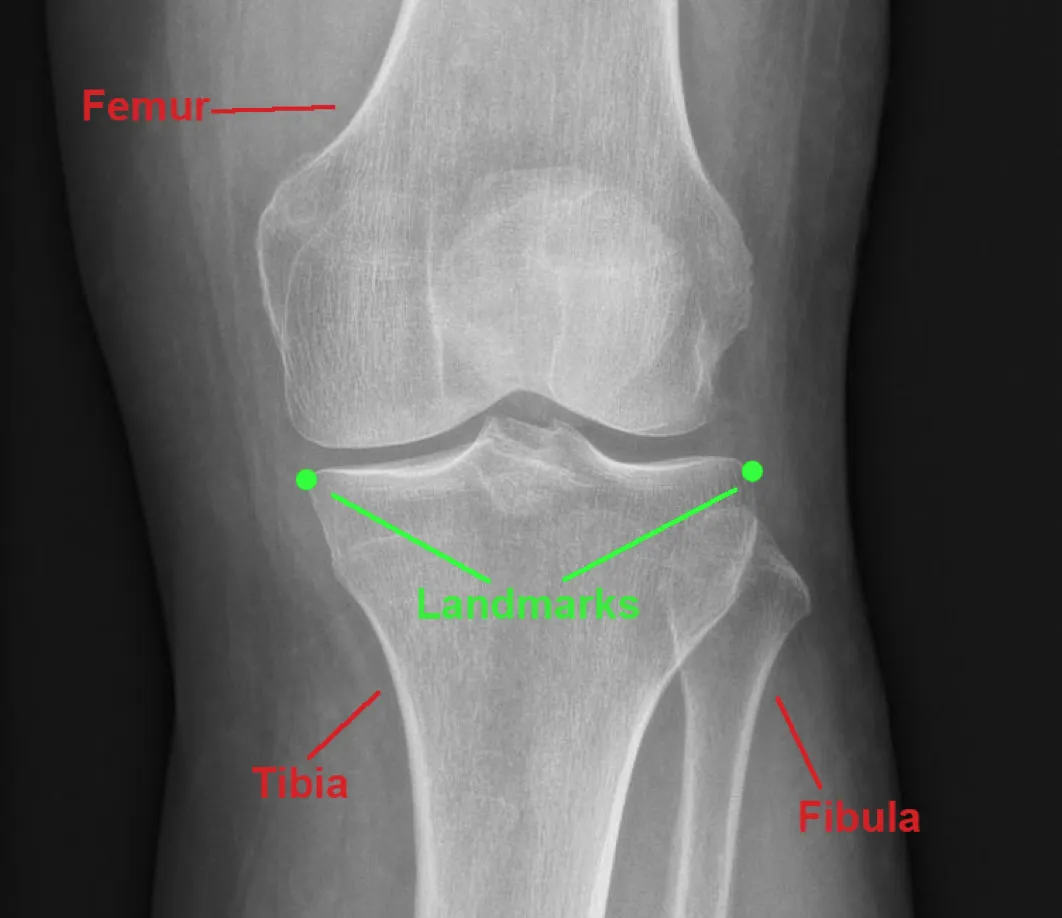

Developed an interactive clinical visualization system at ImageBiopsy Lab for analyzing osteoarthritis progression in knee joints. The platform integrated machine-learning models for automated landmark detection and quantitative measurement extraction from radiographic images, enabling structured visualization of joint-space narrowing and anatomical changes over time. The system translated computational imaging models into an accessible web-based analytical interface for research and clinical evaluation. The project formed the basis of my Bachelor’s thesis under the supervision of Prof. Eduard Gröller.